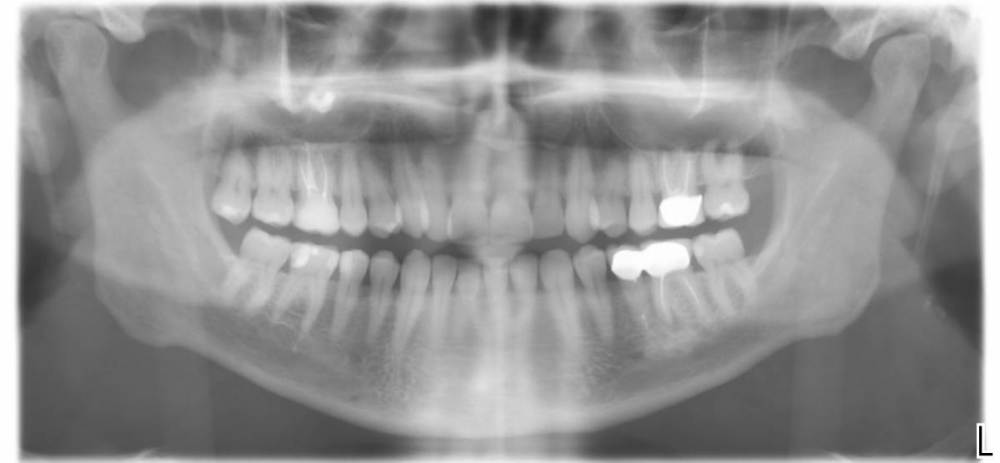

Telder5432 Опубликовано 11 апреля, 2021 Поделиться Опубликовано 11 апреля, 2021 Добрый день, почитав форум, сразу понял, что первым в вопросе должен быть снимок: Приговорили два левых зуба под коронками, верхний и нижний. Говорят, что кисты и там и там. Видимо те, кто хочет заработать, предлагают сразу без разговоров импланты, а другие предлагают попробовать лечить. Почитал в интернете про "чудо метод депофорез" - но вот на этом форуме вижу, что врачи о нем отзываются не очень. Проблема еще заключается в том, что в верхнем зубе в главном канале (если я верно называю) какой-то не вынимаемый штифт (из стекловолокна вроде бы) и на сколько я понимаю не гуттаперча, а что-то твердое. Нижний зуб не болит, я даже не знал, что там киста и вообще проблемы, а вот верхний болел, пропил антибиотики, прошел, но лечить нужно. Посоветуйте, пожалуйста, что делать в моей ситуации? Спасибо большое заранее! Ссылка на комментарий

St. Опубликовано 14 апреля, 2021 Поделиться Опубликовано 14 апреля, 2021 11.04.2021 в 10:08, Telder5432 сказал: "чудо метод депофорез" - но вот на этом форуме вижу, что врачи о нем отзываются не очень. Чудес не бывает, как и волшебной таблетки) Действительно по поводу зубов с воспалением - альтернатив 2 и каждый выбирает что ему ближе. Я придерживаюсь мнения что лучше своего зуба никто ничего не придумал и если можно подороться за свой, то лучше это делать. Беда что не всегда получается. я бы рекомендовала снять коронки и посмотреть что там от них останется, если стенок достаточно - то лечить, если они сильно разрушены или где-то обнаружится к примеру трещина корня, тогда удалять и импланты. Для перелечивания каналов нужно найти доктора эндодонтиста, лучше с микроскопом. Стекловолокно достать можно, это не самая большая проблема. 1 Ссылка на комментарий